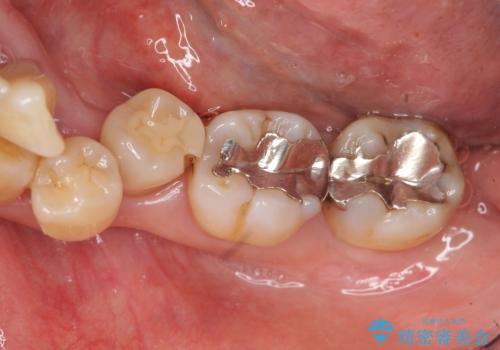

歯周病再生治療と歯周ポケット除去 歯周外科手術

- 他院で歯周病を指摘され、様子見ではなく根本的な治療はないか?とご相談に来院されました。

重度の歯周病で再生療法の適応ではない最後方臼歯は抜去行い、インプラント治療、

がたつきの強い天然歯を矯正治療で整えたのち、再生治療、歯周ポケットを除去する歯周外科手術を行いました。